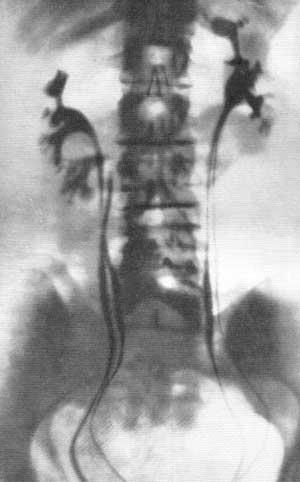

Экскреторная урография при нефроптозе: диагностические изображения